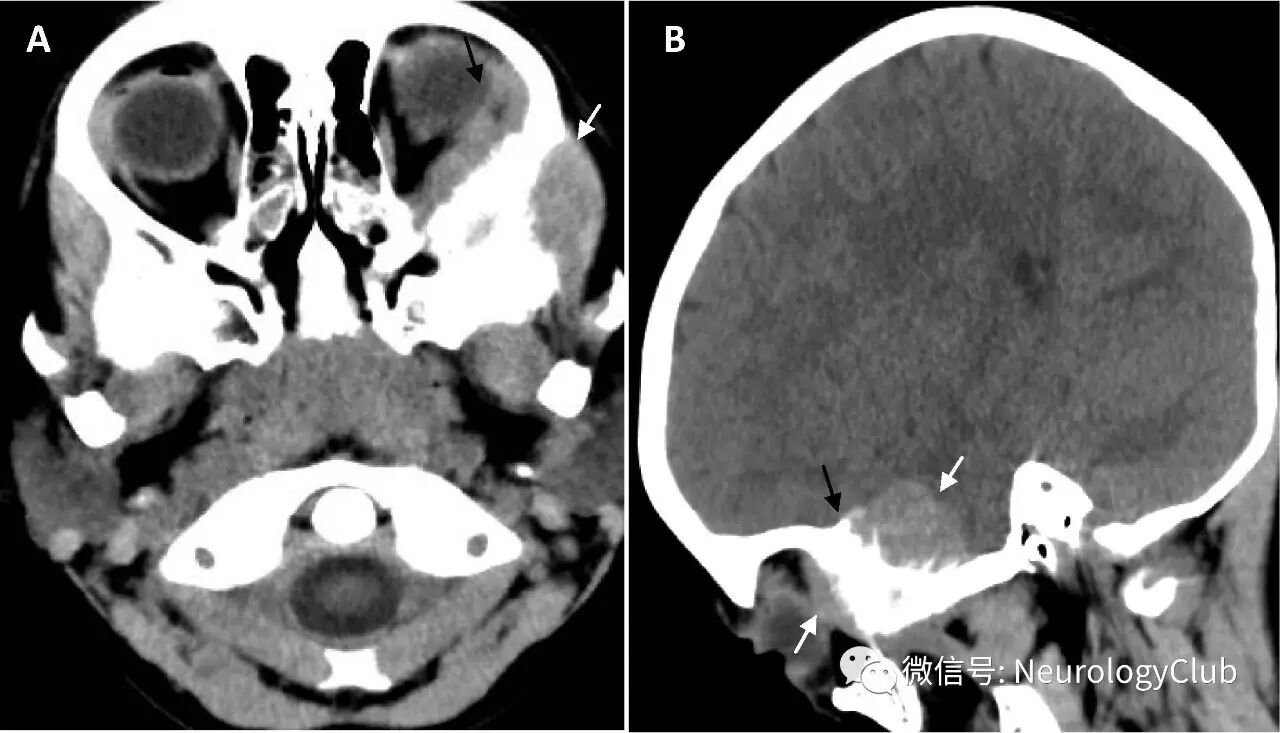

(图2:A:颅底CT骨窗证实累及蝶骨翼的破坏性侵袭性病变;B:冠状位T2WI可见左侧肾上腺神经母细胞瘤)

本例患儿临床,影像学和病理学特点符合转移性神经母细胞瘤,腹部MRI提示原发部位为左侧肾上腺(图2)。

典型的CT或MRI特征为源于眶壁的肌锥外软组织肿块。如本例患者,肿瘤可局部侵袭深入颞下窝结构或颅内,伴眶顶和眶壁骨性破坏以及骨针形成。

肿瘤可为单侧或双侧,不同于横纹肌肉瘤,后者通常为单侧。此外,横纹肌肉瘤可累及前中隔眼眶结构,而神经母细胞瘤通常不会。神经母细胞瘤还可导致硬脑膜和软脑膜转移,伴颅骨受累。